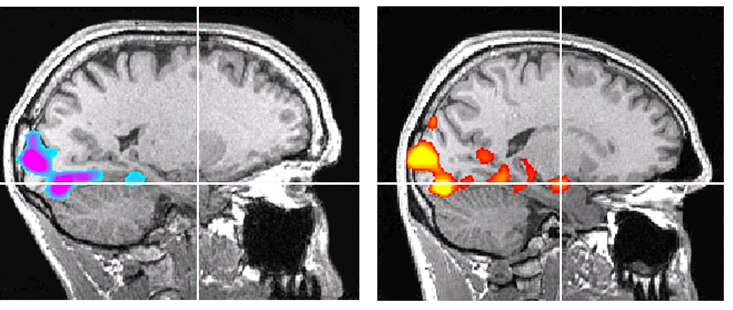

Absence de peur : les scanners comparent le cerveau de Honnold (à gauche) à celui d’un sujet témoin (à droite), un grimpeur d’âge similaire. Les repères indiquent l’amygdale. Alors que les deux grimpeurs regardent les mêmes images stimulantes, l’amygdale du sujet témoin s’illumine, tandis que celle de Honnold reste inerte, ne montrant aucune activité © Jane Joseph

Le technicien James Purl et la neuroscientifique Jane E. Joseph ont placé Honnold dans un appareil d’IRM afin de mesurer son niveau de peur © NGC Network International

Les images défilent, mais son amygdale reste étonnamment silencieuse. Là où celle d’un autre grimpeur, pourtant habitué à l’exposition, s’illumine clairement, celle de Honnold demeure quasiment inactive. Son cerveau perçoit l’information… mais ne déclenche pas de réponse de menace. Un résultat si atypique qu’il a conduit les chercheurs à vérifier à plusieurs reprises les données, tant elles sortaient des standards habituels.